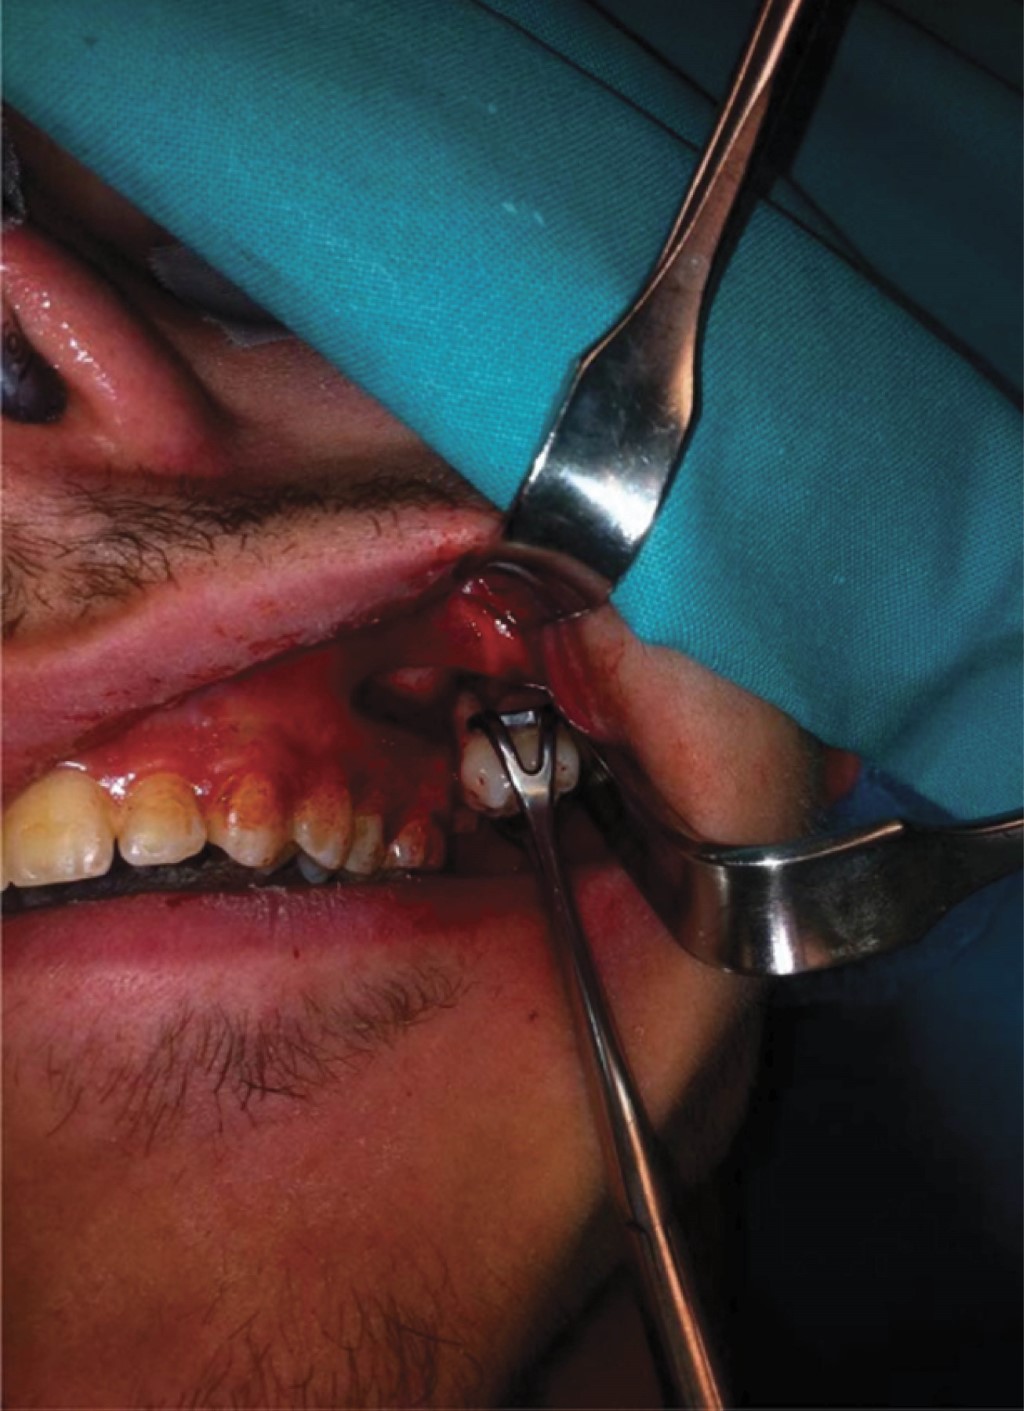

La recuperación de la unidad dentaria desplazada puede ser mediante un abordaje intraoral como fue expresado anteriormente, o extraoral como lo presenta Nadeem A y su equipo en el estudio denominado: A rare case of mandibular third molar displaced into submandibular space: A complication of mandibular third molar extraction10 en el cual mencionan el caso de un paciente masculino de 44 años de edad, en donde en una cirugía anterior ocurrió el desplazamiento del tercer molar inferior izquierdo, al realizar los estudios radiográficos y una tomografía computarizada, se dio a conocer la ubicación exacta del tercer molar el cual se encontró en la zona submandibular (Figuras 5 y 6); el abordaje fue realizado mediante un colgajo lingual, bucal y una incisión en la zona submandibular, ya que la unidad dentaria se encontraba muy profunda, sin embargo, con buena iluminación lograron encontrar la unidad dentaria y con una cureta se pudo traccionar el molar hacia el exterior (Figura 7). A diferencia de los casos de desplazamiento de terceros molares, en los cuales el único abordaje posible es de manera extrabucal, como expresan Shruthi TM y colegas en el estudio tipo reporte de caso: Removal of Displaced Maxillary Third Molar Using Modified Gillie's Temporal Approach11 donde presentan a un paciente femenino de 26 años de edad cuyo tercer molar superior derecho fue desplazado durante la osteotomía del hueso maxilar Le Fort 1, para el reposicionamiento del hueso maxilar por aumento de la dimensión vertical; el tercer molar fue desplazado hacia los tejidos más profundos y no se podía palpar, en la misma cirugía se intentó recuperar el tercer molar a través de la incisión intraoral que ya se había realizado para la osteotomía, pero no se tuvo éxito. Se indicó la realización de una tomografía computarizada lo cual reveló que el tercer molar fue desplazado hacia la fosa infratemporal (Figura 8). Por su ubicación se decidió realizar un abordaje extraoral mediante un "abordaje temporal de Gillies modificado", el tercer molar fue encontrado y recuperado con éxito. De la misma manera, Oliveira MMM y colaboradores en el estudio Third Molar Displacement into Submandibular Space,12 reportan el caso de un paciente masculino de 21 años quien durante la cirugía para la extracción del tercer molar inferior izquierdo experimentó el desplazamiento de un fragmento de la unidad dentaria. Durante la cirugía el operador intentó recuperar el fragmento pero no tuvo éxito. Se indicó la realización de una tomografía computarizada Cone Beam, para la revisión y ubicación del mismo, el cual se encontró en el espacio submandibular (Figura 9). Para la recuperación del fragmento se decidió realizar un acceso extraoral en la región submandibular bajo anestesia general, la unidad dentaria se pudo recuperar con éxito (Figura 10).

Figura 9